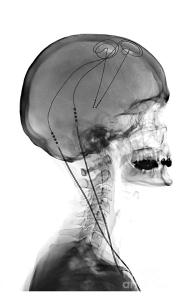

Deep brain stimulation (or DBS) is a treatment method that involves embedding electrodes into the brain to help modulate the brain activity involved in movement.

First introduced in 1987, deep brain stimulation consists of three components: the pulse generator, an extension wire, and the leads (which the electrodes are attached to). All of these components are implanted inside the body. The system is turned on, programmed and turned off remotely.

Source: Ucdmc

The electrodes that are implanted deep in the brain are tiny, and the very tip of them has small metal plates (each less than a mm in width) which provide the pulses that will help mediate the activity in the brain.

DBS electrode tip. Source: Oxford

The electrode extends up into the leads (or extension wire) which continue up and out of the brain, across the top of the skull, down the neck and to the pulse generator which is generally located on the chest.

Xray image demonstrating the leads. Source: Fineartamerica

DBS reduces inhibition inside specific structures in the brain, which allows individuals with Parkinson’s to move more freely (Click here to read a previous SoPD post on DBS).